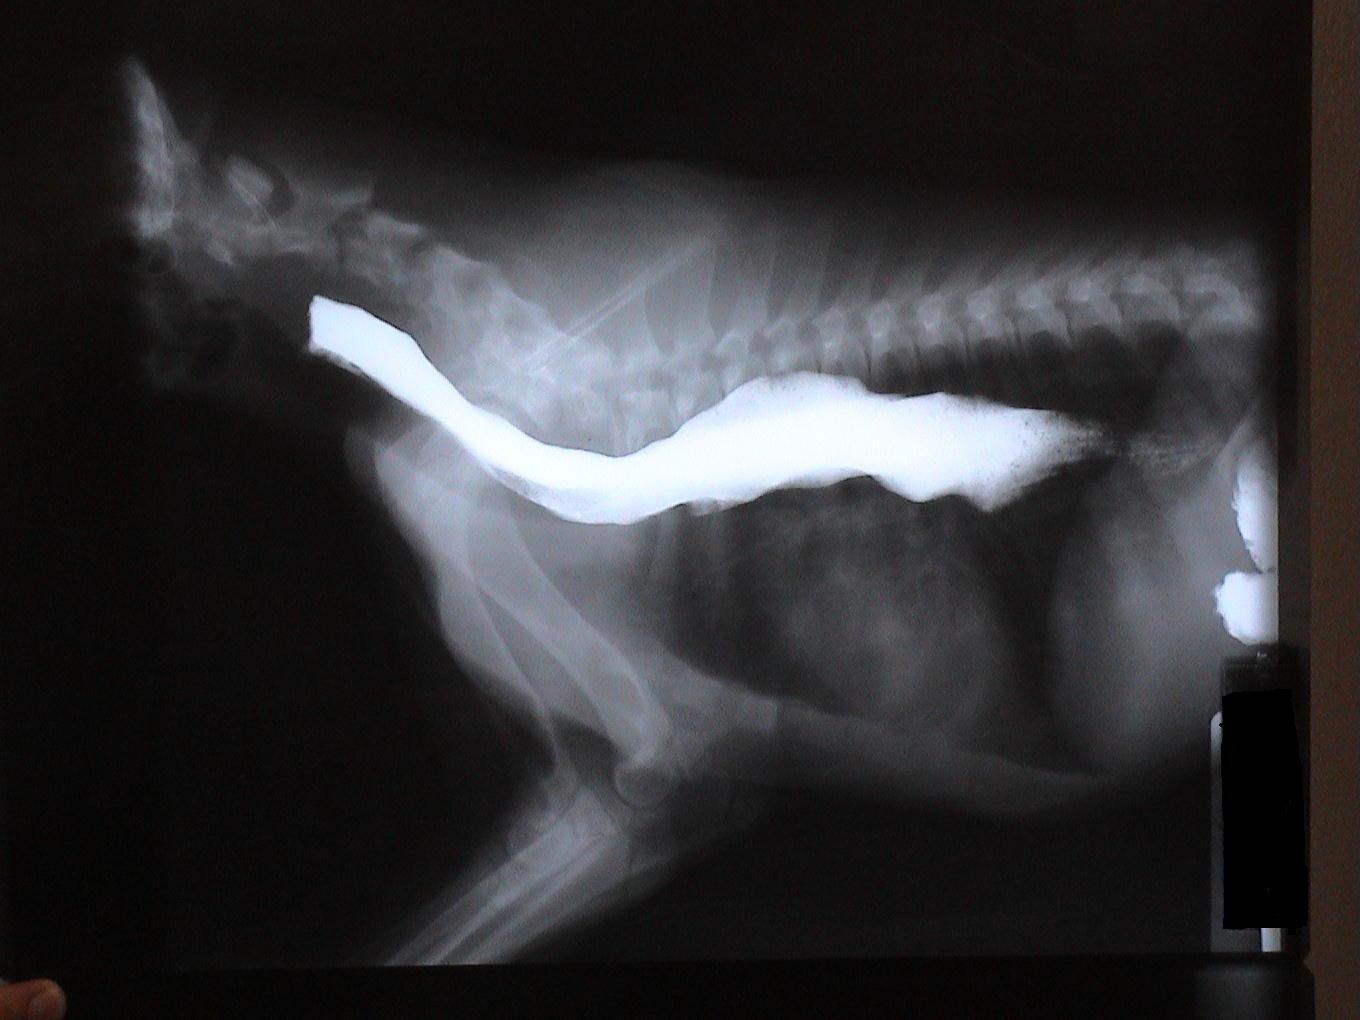

Chief - Megaesophagus-Congenital

This x-ray demonstrates one film in a barium study. (Barium is a liquid contrast media that shows up as a bright white substance on an x-ray. It can be used to demonstrate the size and shape of structures that do not show up well on regular x-rays.)

The large white tubular structure is an abnormal esophagus or megaesophagus. Animals can be born with a megaesophagus (congenital) or can develop one secondary to several conditions (acquired).

Because of its enlarged size, food is unable to properly move from the mouth to the stomach. Thus, animals with megaesophagus will often regurgitate whole/undigested food. Aspiration of regurgitated food and secondary pneumonia is the most common complication in animals with a megaesophagus.

It is often not possible to "cure" a megaesophagus since surgical options are limited. Thus medical management is often the only treatment available. Feeding multiple, small, softened meals from an elevated position can significantly decrease regurgitation episodes. Special thanks to Chief's owners for allowing us to share this case.